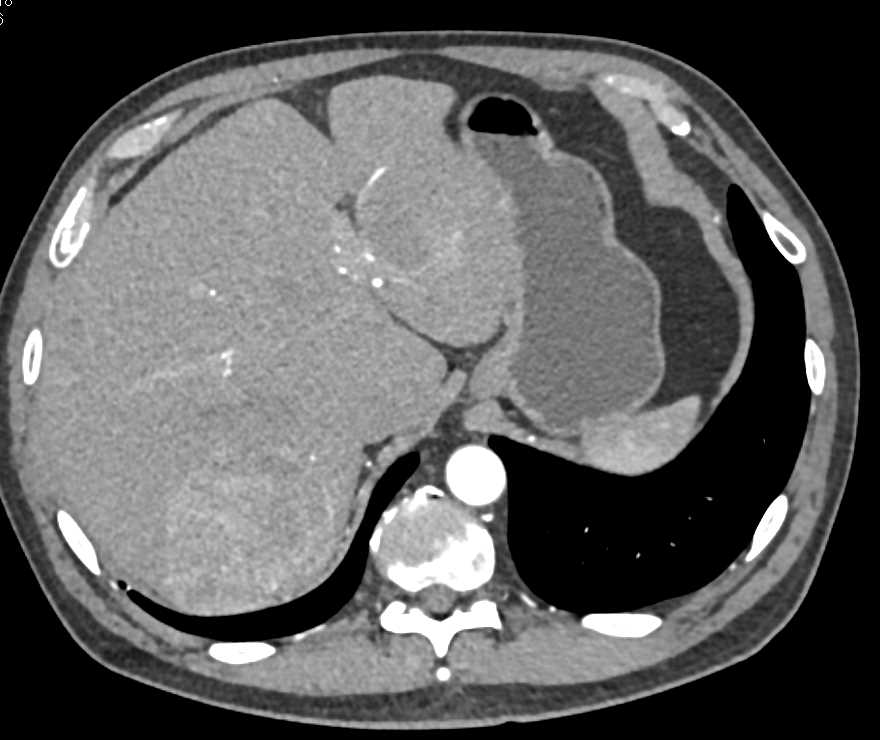

Carcinoid Tumor with Desmoplastic Reaction